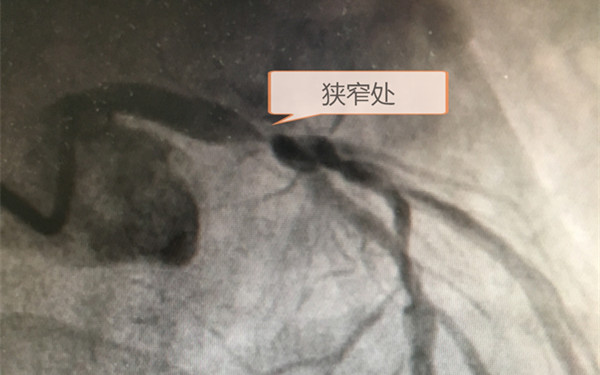

10月21日一位61岁的男性患者因反复胸骨后烧灼不适16天来我院就诊,因高度怀疑冠心病收住我院心内科,10月22日下午16时紧急为其行冠状动脉造影术,结果示:LM末端90-95%狭窄,LAD开口80-90%狭窄,LCX开口99%狭窄,RCA远段50—60%狭窄。

心内科医师下达病危通知并联系外科会诊,17:30分心外科盛存见主治医师会诊后转入心外科。考虑患者冠心病、左主干病变、两支病变,重度狭窄,病情危重,随时有心源性休克、急性心肌梗死及猝死可能,病情危重,命悬一线,紧急请示心外科主任张申教授及吴联合副主任医师。经科室讨论后,张申主任指示连夜完善术前化验检查,吴联合副主任医师积极与会诊家属沟通病情,并与手术室、麻醉科、体外循环科等相关手术团队人员沟通,暂停明日常规手术,一路绿灯,急诊行冠脉搭桥术。